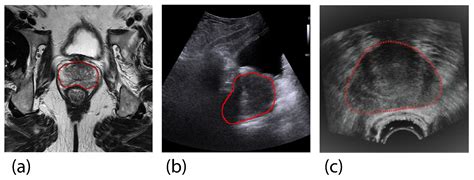

Transrectal Ultrasound (TRUS)

Transrectal ultrasound is a more accurate method for estimating prostate volume. A probe is inserted into the rectum to produce ultrasound images of the prostate. The images are then used to calculate the prostate’s volume using the formula for an ellipsoid:

Volume = 0.52 × (length × width × height)

This method is widely used due to its accuracy and non-invasive nature.

Magnetic Resonance Imaging (MRI)

Magnetic resonance imaging provides detailed images of the prostate and surrounding tissues. MRI is particularly useful for detecting prostate cancer and assessing the extent of the disease. It can also provide accurate measurements of prostate volume. However, MRI is more expensive and time-consuming compared to TRUS.